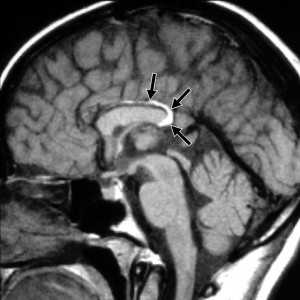

МРТ головного мозга. Сагиттальная Т1-взвешенная МРТ. Липома мозолистого тела.